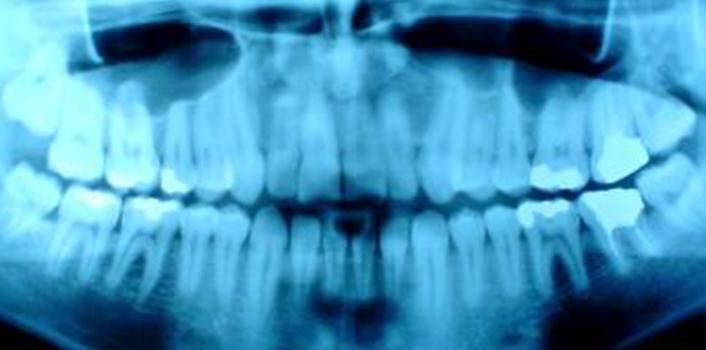

When we open our jaws, the lower jaw bone glides down and slightly forward. In order for this to happen, the rounded edge of our jaw bones (known as the condyle) glide across a small lubricated disk (the articular disk) that separates the jaw bone from the base of our skull. However, sometimes the disk may be out of place, or out of shape, which causes the lower jaw bone to rub against the bottom of our skull.

The noise you hear when this happens is called crepitus.